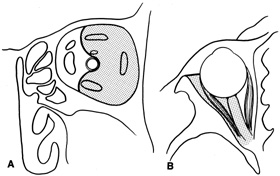

complete hemostasis. Indications Lateral orbitotomy provides excellent access to deep lesions in the subperiosteal, peripheral, or

intraconal space lateral to the optic nerve (Fig. 8A, B).  Fig. 8. Coronal (A) and axial (B) views in an illustration of areas (shaded) amenable to lateral

orbitotomy. Fig. 8. Coronal (A) and axial (B) views in an illustration of areas (shaded) amenable to lateral

orbitotomy.